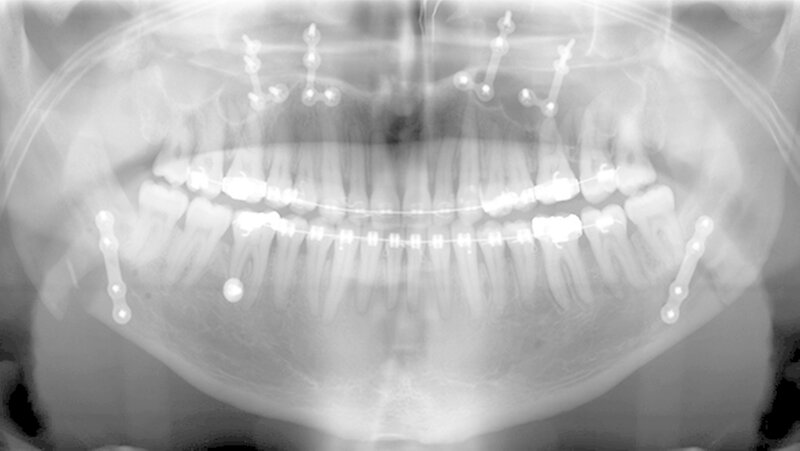

Der Patient stellte sich erstmals 2010 in der Stuttgarter MKG-Spezialsprechstunde vor. Im ersten Schritt wurde der Tumor an der Hirnanhangdrüse über die Nase entfernt. In interdisziplinärer Zusammenarbeit mit einem Fachzahnarzt für Kieferorthopädie wurden im ersten Behandlungsabschnitt die Zahnbögen ausgeformt. Um den Oberkiefer in der Breite zu dehnen, führten die Stuttgarter Zahnärzte im Oktober 2012 eine chirurgisch unterstützte Gaumennahterweiterung durch.

Nach dreidimensionaler Planung im zahntechnischen Labor, in dem die Bissschlüssel konventionell hergestellt wurden, wurden dann ein Jahr später beide Kiefer operativ mobilisiert. Hierzu wurde von einem Schnitt im Mund der Oberkieferknochen freigelegt.

Mit einer Säge wurde ein gezielter Knochenschnitt durchgeführt. Nach der Präparation wurde der zahntragende Abschnitt des Oberkiefers vom restlichen Gesichtsschädel gelöst. Erst wurde die Bisssituation anhand des Bissschlüssels exakt eingestellt, dann mit 2 mm dicken Osteosyntheseplatten aus Titan der Knochen in der neuen Position mithilfe von Titanschrauben fixiert.

Im Unterkiefer erfolgte dann die Schnittführung im Zahnfleisch hinter dem letzten Backenzahn beidseits. Nun wurde der Unterkiefer mit spezieller Technik durchtrennt um die zahntragende Basis vom gelenktragenden Knochenabschnitt des Unterkiefers zu verschieben. Bei der Präparationwurde der im Unterkieferknochen verlaufende Gefühlsnerv der Unterlippe sorgfältig geschont.

Die neue Position wurde mit einem zweiten Bissschlüssel, der die endgültige Bisssituation einstellt,zugeordnet und mit Osteosyntheseplatten und -schrauben gesichert. Die Operation ging mit einem stationären Aufenthalt von nur fünf Tagen einher.

Das deutlich harmonischeres Profil drei Monate nach der Operation: Im Mai des nachfolgenden Jahres wurden die Metallplatten in einem ambulanten Eingriff wieder entfernt. Eine Multibandapparatur hält die Zähne noch "in der Reihe". Der Patient kann heute dank der individuellen innovativen Behandlung ein normales Leben führen, die Gesichtsästhetik und seine Kaufunktion sind vollständig wiederhergestellt.